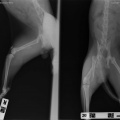

Kass kukkunud ilmselt aknast alla, tagumise käpa luumurd.

kiisu pareneb. Tal oli puusaluu murd (unustasin pildid lisada siia albumisse, kohe teen).